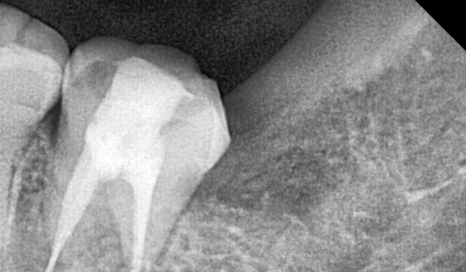

이 경우에는 단순 엑스레이만으로는

신경과의 거리를 정확히 판단하기 어렵기 때문에

보다 안전한 발치를 위해 CT 촬영을 진행했습니다.

240920 상일동 사랑니 매복 방치

CT로 확인해 보니

신경관과 사랑니 뿌리가 매우 근접해 있어

발치 시 각별한 주의가 필요한 상황이었습니다.

240920

그래서 이 환자분은

치아를 한 번에 힘으로 빼는 방식이 아니라,

사랑니를 여러 조각으로 나누어

신경 쪽으로 힘이 전달되지 않도록

조심스럽게 분할 발치를 계획했습니다.